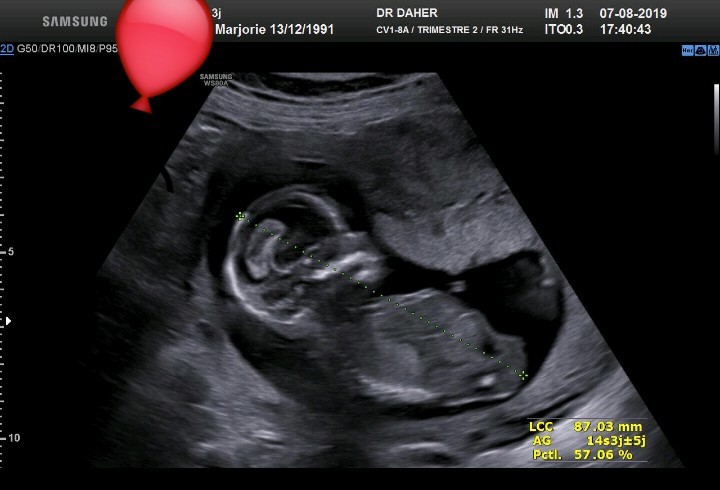

Pour en savoir plus Grossesse semaine par semaine Semaine 14Échographie de la petite soeur de Naomi, à 31 semaines de grossesse La tête est positionnée vers le bas et on estime qu'elle pèse environ 4 lbs 9 oncesJ'en avais les larmes aux yeux J'ai réentendu son coeur mais cette fois c'était plutôt "surround"!

Certains de ces chiffres correspondent à la table des percentiles du fœtus ils vous indiquent comment votre bébé grandit Lorsque la future maman fait une échographie, les résultats ne sont pas toujours faciles à interpréter La plupart font référence aux percentiles et indiquent comment le fœtus se développe dans le ventre Cela correspond aux 9, 10 et 11eme semaines de grossesse (soit environ 3 mois de grossesse) Cette échographie dure environ 30 minutes Elle permet d'examiner la tête, le thorax, les membres, le ventre, les différents organes et notamment le cœur du fœtus afin de s'assurer de la vitalité fœtaleL'échographie dans les 23 semaines de grossesse est réalisée uniquement pour des raisons médicales À quoi ressemble un enfant à cette époque?